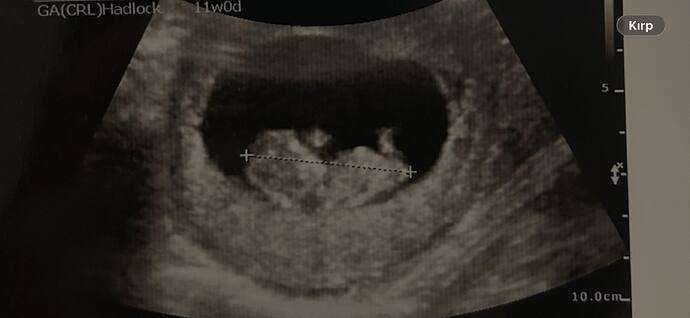

Kızlar kesesine göre sizce cinsiyeti nedir

Çok net değil ama duruş kız bebek gibi canım daha net bir fotoğraf var ise paylaşabilirsin

Çok net değil ama kese kız kesesi gibi net fotoğraflari olunca tekrar atarsın cnm

Bacak arasından bir şey var Kordon ise ama kız bebek gibi duruyor canim